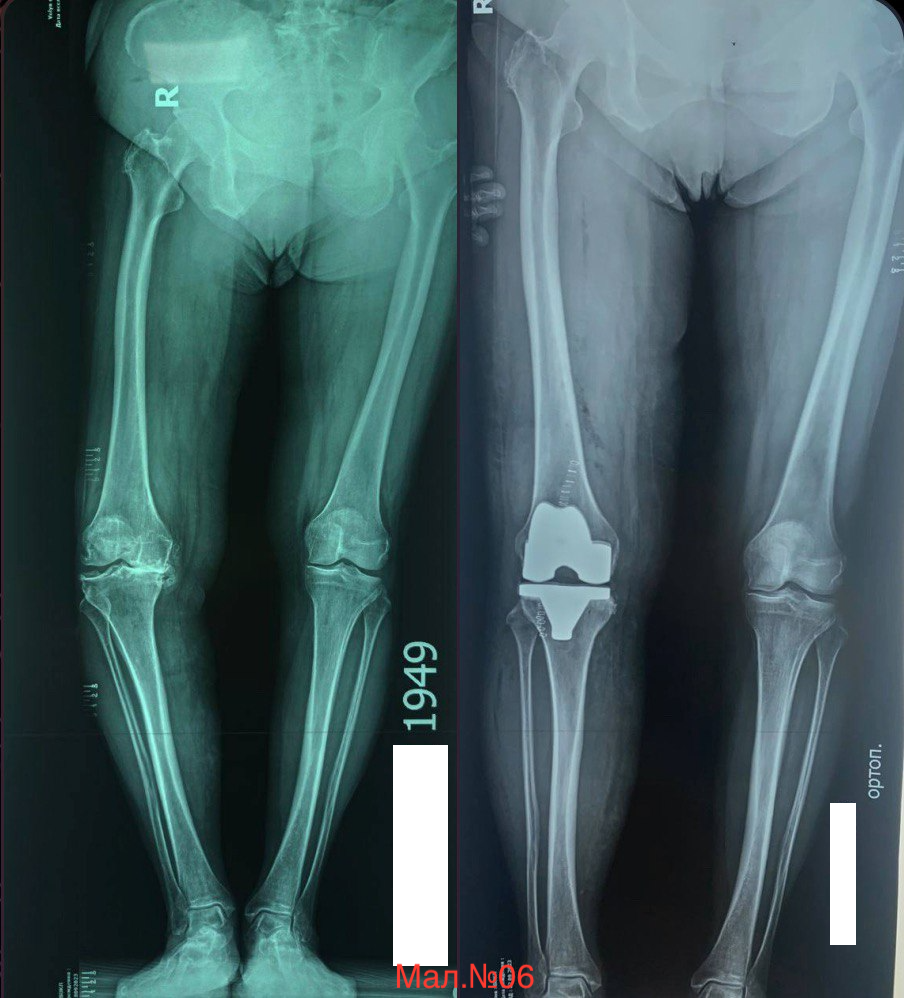

photo_2023-12-13 17.20.08